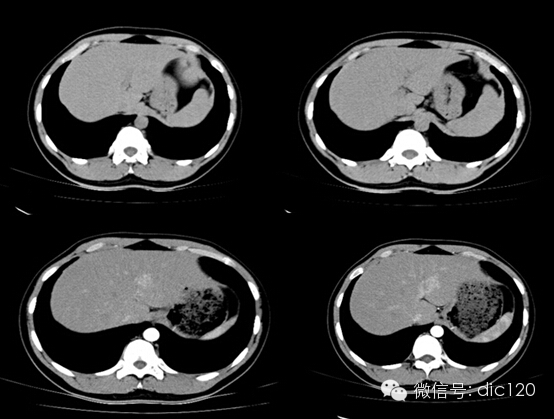

影像表現(xiàn):CT平掃與正常肝組織呈等密度,密度均勻,動(dòng)脈期病灶快速明顯均勻強(qiáng)化,中心見(jiàn)小片狀低密度影(瘢痕),門(mén)脈期及延遲期對(duì)比劑快速退出呈等密度,中央低密度影延遲強(qiáng)化。MRI腫塊T2WI為稍高信號(hào),中央高信號(hào)。動(dòng)態(tài)增強(qiáng)掃描動(dòng)脈期均顯著增強(qiáng),門(mén)脈期輕度增強(qiáng),延遲期瘢痕強(qiáng)化。

FNH具有離心性血液供應(yīng)及二條血液引流途徑。FNH的典型CT表現(xiàn)包括增強(qiáng)早期腫瘤呈彌漫均勻強(qiáng)化,在門(mén)靜脈期或門(mén)靜脈后期成等密度,病灶內(nèi)可見(jiàn)中心低密度瘢痕及輻射狀分隔,腫瘤周圍有薄而不完整的包膜樣血管。瘢痕是FNH 另一個(gè)重要影像學(xué)表現(xiàn),尤其是延遲掃描瘢痕強(qiáng)化為其特征。